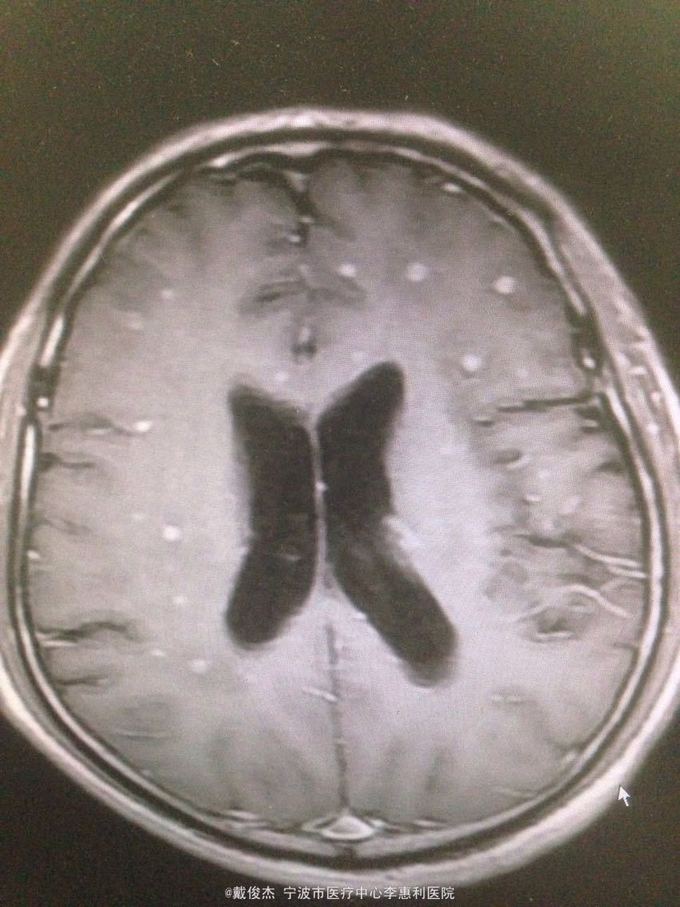

查体:神志清,双肺啰音,颅神经阴性,颈抵抗,四肢肌力正常,双巴氏征阴性 辅查:脑脊液压力380mmH2O,细胞4100/ul,多核90%,单核10%,蛋白223mg/ml。胸部CT示:两肺多发粟粒小结节。头颅MRI示:双侧大脑半球、脑干、小脑多发病灶。

诊断:结核性脑炎,肺结核 处理:抗痨治疗,激素,降颅压,保护神经和对症支持治疗